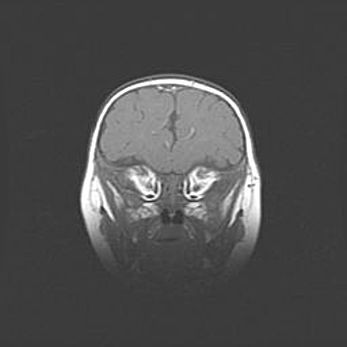

Аномалия Денди-Уокера. Признаки гипоплазии мозолистого тела.

Возраст: 5 месяцев 3 дня

Вес: 5550 г

Пол: мужской

Окружность головы: 39 см

Срок гестации: 40 недель

Аномалия Денди-Уокера – это порок развития головного мозга, для которого характерна триада симптомов: гипотрофия или аплазия червя мозжечка и/или полушарий мозжечка, расширение четвёртого желудочка с формированием ликворной кисты задней черепной ямки, гипертензионная гидроцефалия различной степени.

Гипоплазия мозолистого тела относится к дефектам внутриутробного этапа развития мозговой ткани, возникающим в процессе закладки структур головного мозга, что происходит на начальных этапах развития эмбриона.